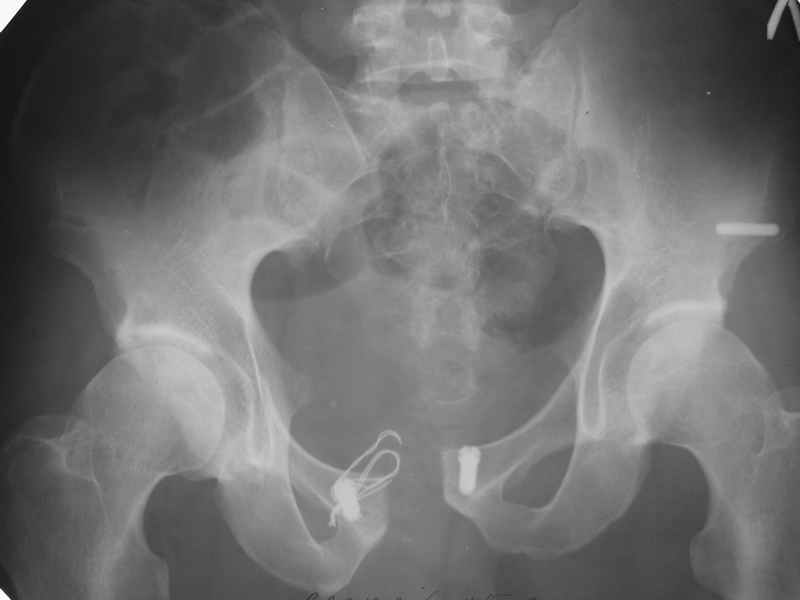

Здесь слайды случая больного с политравмой, включающей сегментарный перелом бедра и повреждение таза с нарушением тазового кольца, разрыв симфиза и перелома крестца зон 2 и 3.

На множественных слайдах важные моменты операции. Хотел бы подчеркнуть, как важно иметь возможности всех необходимых ренгенограмм, включая компютерную томографию и стандартных внутритазовых рентгенограмм (инлет и оутлет).